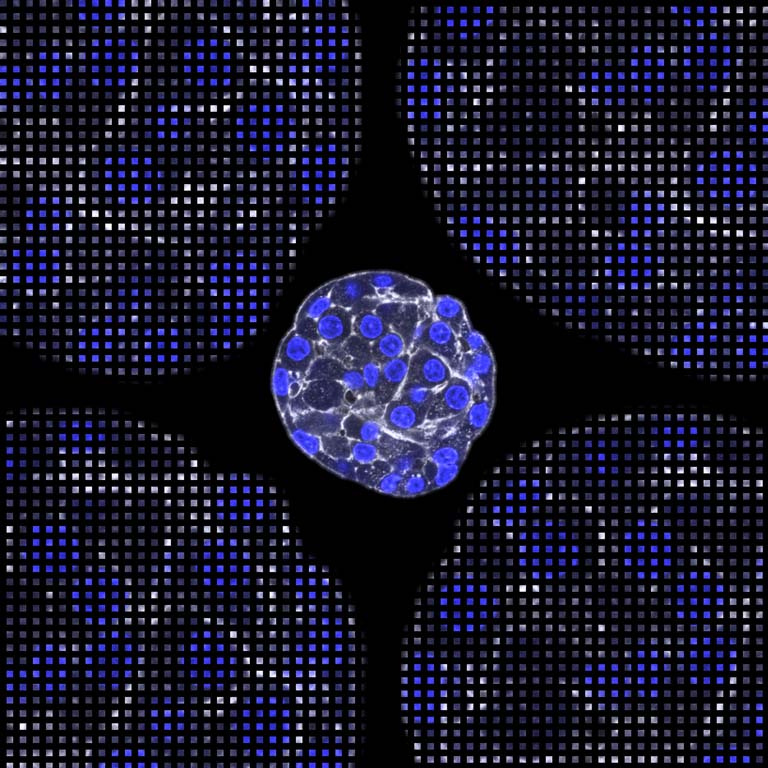

Diabetes is a common disease in which the glucose regulating cells in the pancreas, that form spheroids called islets, fail at their function. There is currently no reliable and predictive in vitro model of the pancreas to allow researchers to develop a cure for diabetes. We are working on developing a physiologically relevant in vitro model for the endocrine pancreas using islets that look like this. This image shows a single islet. The 4 corners are replicates that have been blown up into small squares for visualization purposes only.